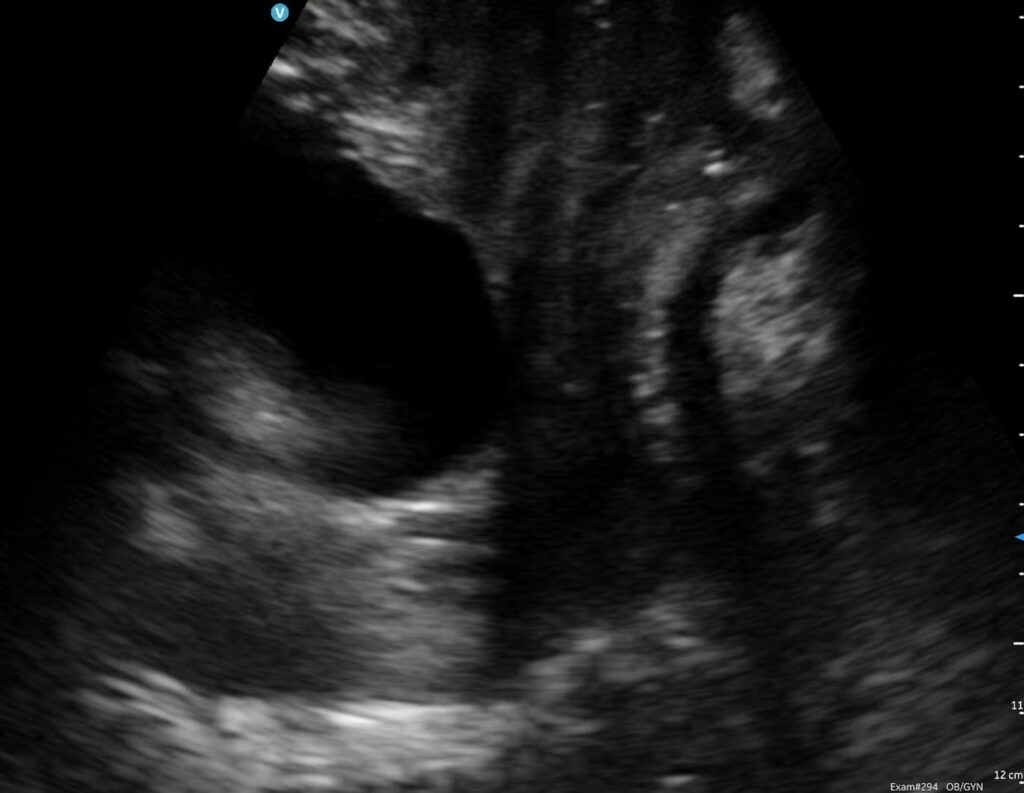

Dynamic ultrasound scanning of the pelvic floor and bladder through the abdomen

Here you can see the bladder clearly (the black bit) and the movement of the pelvic floor downwards and upwards at the base of the bladder during a pelvic floor contraction. We can assess pelvic floor function in lying and standing. We can also assess whether you are fully emptying your bladder with ultrasound.